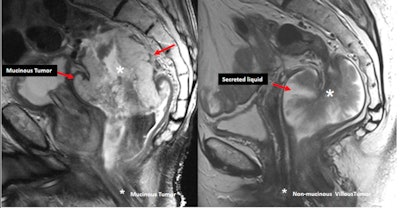

"Mucinous tumors are defined histologically as those containing 50% or more of stromal mucin. They have a worse prognosis than similarly T-staged non-mucinous tumors," the authors noted. "It is incorrect to call a tumor that secretes a large amount of mucin into the lumen, 'mucinous.' "

Mucinous tumors contain more than 50% of stromal mucin (left, sagittal T2-weighted MR image shows high signal intensity within the tumor). They must not be confused with non-mucinous lesions that secrete a large amount of liquid into the lumen (right).Mucinous tumors typically show large areas of low attenuation and intratumoral calcification on CT and high signal intensity on T2-weighted MR images due to the presence of mucin pools. High signal intensity is defined as intensity similar to, or brighter than, the mesorectal fat. T2-weighted sequences with fat suppression, diffusion-weighted imaging (DWI) b0, or a dynamic contrast-enhanced series are helpful for diagnosis, they added.